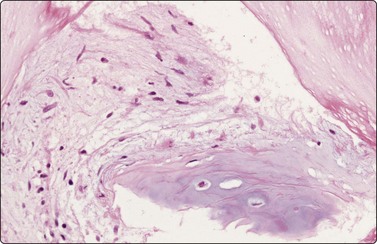

Pneumoconioses

Birefringent silica and collagenous tissue (Fig. 8.13) or asbestos bodies may help confirm silicosis or exposure to asbestos.203 However, concomitant malignancy, tuberculosis or other infections may be the cause of the localized opacity in these patients.204

image image

Fig. 8.13 Anthraco-silicosis; progressive massive fibrosis

Bilateral upper zone/hilar lung masses in a miner. Dense masses of macrophages and fibrous tissue (A, H&E, MP; B, H&E, HP).